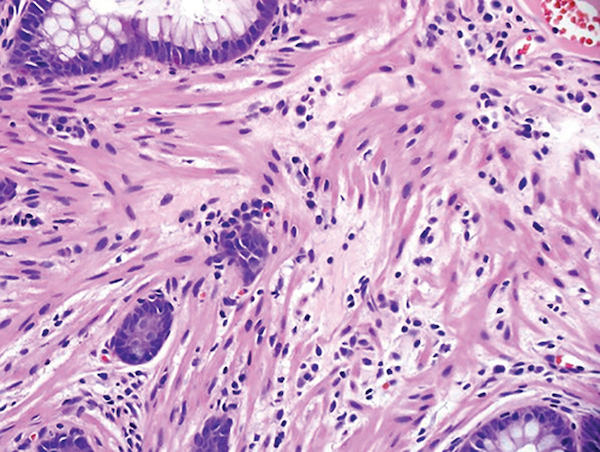

A 66-year-old woman is admitted to the hospital with a 1-day history of abdominal pain and hematochezia. Her prior medical history is notable for poorly controlled type II diabetes mellitus, hypertension, hyperlipidemia, osteoarthritis, glaucoma, and alcoholic cirrhosis. She drinks a half pint of alcohol per day and has done so for 30 years. She smokes 1 pack of cigarettes per day and uses cocaine 3-4 times per month. Her last cocaine use was 3 days prior to admission. She takes ibuprofen 400-800 mg 2-3 times a day as needed for pain. Admission laboratory tests results reveal WBC 9,500/µL, hemoglobin 10 g/dL, INR 2.1, hemoglobin A1c 13.4, FOBT positive, C. difficile negative. She is observed in hospital and prepared for colonoscopy, which reveals the lesion shown in FIGURE A. Biopsy of this lesion is shown in FIGURE B. Which of the following therapies is most appropriate for this condition?